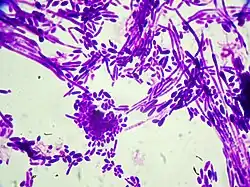

Candida dubliniensis

![]() Wybarwione komórki (powiększenie 1000 x) | |

Candida dubliniensis D.J. Sullivan, Western., K.A. Haynes, Dés.E. Benn. & D.C. Coleman – gatunek mikroskopijnych grzybów zaliczany do drożdży[1].

Gatunek kosmopolityczny (występujący na całym świecie)[2], również w Polsce[3]. Po raz pierwszy opisano go w 1995 r., dawniej nie był odróżniany od Candida albicans, z którym jest blisko spokrewniony[2].

Kolonie C. dubliniensis dobrze rosną w temperaturach 30 i 37 °C na podłożach hodowlanych rutynowo stosowanych do hodowli gatunków Candida. Na podłożach stałych, takich jak agar Sabourauda lub agar z dekstrozą ziemniaczaną (PDA), mają kremowo-biały kolor, podobny do tych tworzonych przez Candida albicans, jednakże, w przeciwieństwie do C. albicans, izolaty C. dubliniensis rosną słabo lub wcale w temperaturze 42 °C. Istotną różnicą pomiędzy C. albicans i C. dubliniensis jest niezdolność tego ostatniego do ekspresji aktywności β-glukozydazy. Cecha ta stanowi podstawę wiarygodnego testu umożliwiającego rozróżnienie tych dwóch gatunków[2].